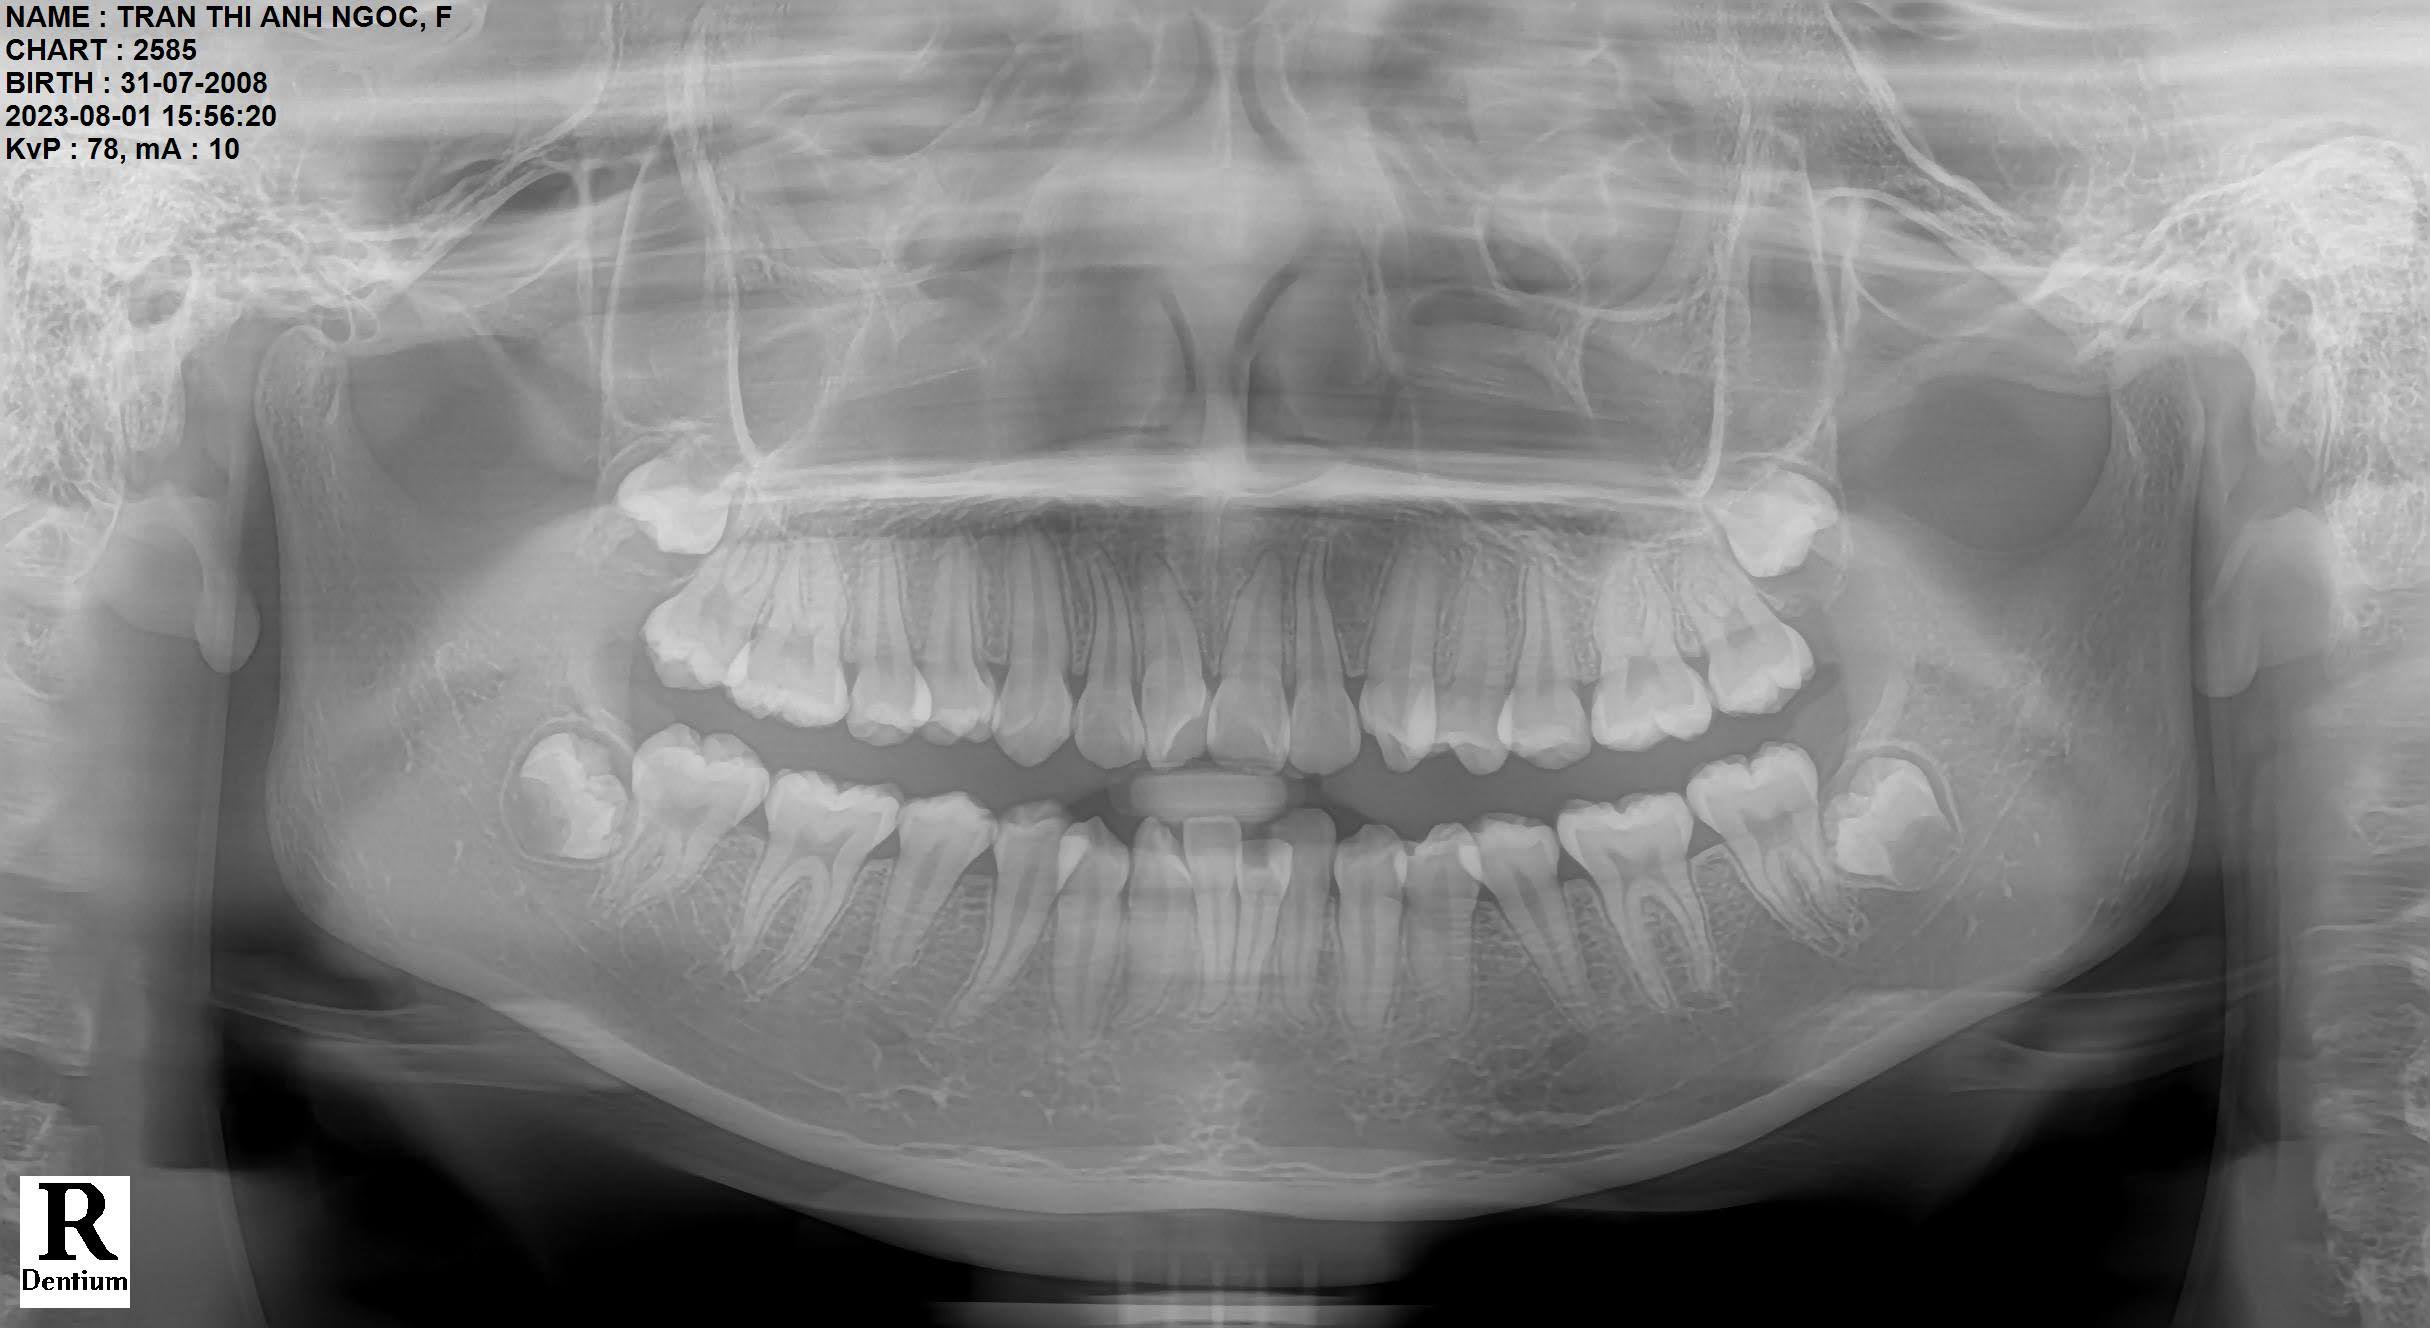

- Phim toàn cảnh Panorama: Đây là phim Xquang giúp bác sĩ có được một các nhìn tổng thể về xương hàm của bạn, xác định chính xác số răng đã mọc, răng mọc ngầm (nếu có), xoang hàm, khớp thái dương hàm. Phim Panoram là một phim thường quy, cơ bản cần có trong chỉnh nha.